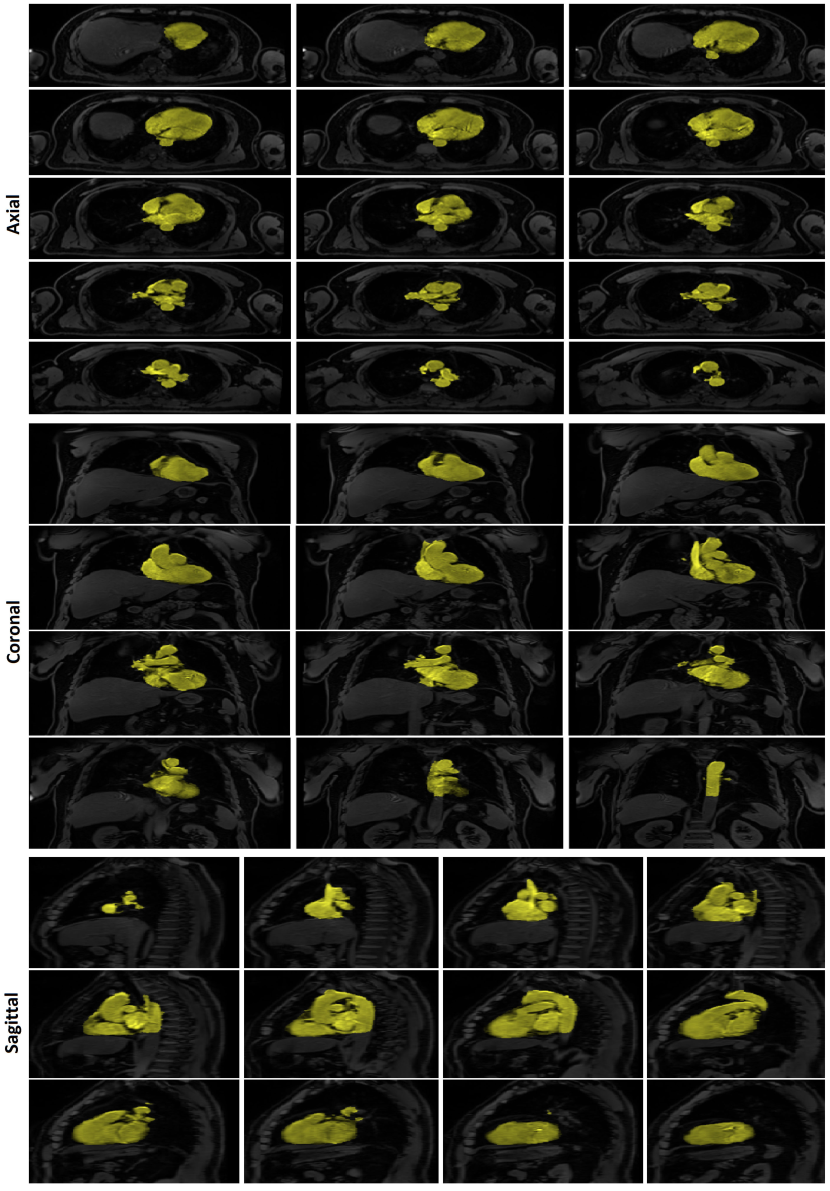

The classification priors of the samples could be estimated by any method such as the multiatlas registration or the hierarchical random forest classifier proposed in [Fallah 2018a, Fallah 2018b, Fallah 2019b, Fallah 2019a]. This happened when the classification probabilities estimated by those methods were not accurate enough to be considered as final classification probabilities (posteriors) rather as initial classification probabilities (priors). For example, the classification probabilities estimated by the proposed forest could not differentiate different kinds of cardiac adipose tissues on fat-water MR images. They could only differentiate the overall adipose tissues from nonadipose tissues. This was due to lack of spatial information in the forest, similar contrasts and features of the cardiac adipose tissues, and weak boundaries between them. The cardiac adipose tissues were spatially close to each other and separated only through thin septa which were hardly detectable under spatial resolution of standard clinical scanners at 3 T. Figure 1 shows voxelwise classification probabilities estimated by the proposed forest for the cardiac adipose tissues and the resulting segmentations on various slices of a fat image. Figure 2 shows overall segmentations of the cardiac adipose tissues based on the voxelwise classification probabilities estimated by the proposed forest on some axial slices of a fat image. Despite inaccuracies of the priors, they, features, and the spatial (neighborhood) relationships of the samples could pave the way for another classifier such as the neighborhood graph to classify the samples more accurately. For example, the priors could approximately localize an addressed object in an image and thereby speed up or reduce the complexity of its accurate segmentation. The more accurate classification probabilities were called the posteriors. Accordingly, the neighborhood graph was supposed to estimate the classification posteriors of every sample (vertex) with regard to its features, its priors, and its spatial (neighborhood) relationships with other samples of the same resolution .

The graphs proposed in section 3 and section 4 tried to implicitly or explicitly detect boundaries between different classes (e.g. objects) in spatial domain (e.g. image). The implicit boundary detection used the Tukey’s function of the features differences of the connected samples and the explicit boundary detection applied a 3D Sobel operator to each intensity channel of the samples. Both of these techniques could enhance the accuracies of a classification in spatial domain. However, their performance was limited when the features of different classes were similar or the boundaries were too weak to be detected. An example of these cases was segmentation of cardiac adipose tissues on fat-water MR images. As shown in Figure 1 and Figure 2 the random forest classifier proposed in [Fallah 2018a, Fallah 2018b, Fallah 2019b, Fallah 2019a] could only detect the overall adipose tissues but could not differentiate different kinds of it. The neighborhood graph proposed in section 3 or section 4 took the priors, the features, and the classification reliabilities of the samples and applied an implicit or explicit boundary detection. This could enhance the accuracy of the segmentation of the cardiac adipose tissues on fat-water MR images but the performance was still unsatisfactory. Figure 7 shows the voxelwise classification posteriors estimated for these adipose tissues by the implicit and/or explicit boundary detection on two axial slices of a fat image. To tackle features similarities and undetectable boundaries between different classes in spatial domain, we further extended the spatial feature-based subgraph by guiding the classification through additional information. These information got encoded into a diffusion-based susceptible-infected-recovered (SIR) model proposed in [Bampis 2017].